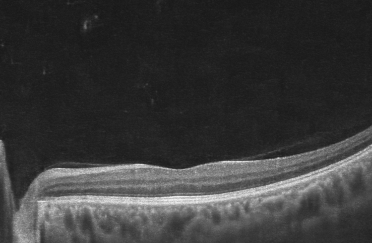

Macular Degeneration

29 January 2024

What is Macular Degeneration? Age-Related Macular Degeneration (AMD) is a common eye condition where the central portion of the retina, known as the macula, gradually loses its ability to see. Often associated with the aging process, AMD tends to be more prevalent among individuals ...